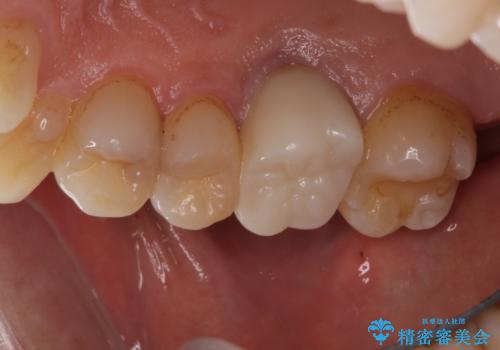

左上で効果を実感して頂き、その後右上もご希望されました。合計3本の歯を治療しました。

腫れもなくなり、見た目もきれいになったため、右上もご希望されて計3本の歯を治療しました。患者様には大変満足して頂きました。